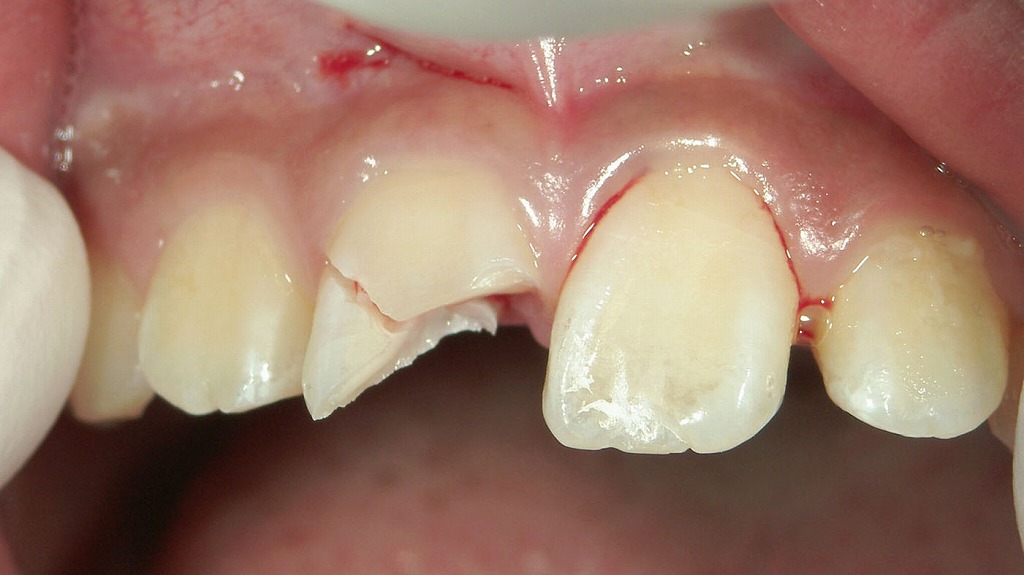

折れた失活歯の応急処置:レジンで一時的に修復

赤矢印で示されている前歯は、神経が無い(失活歯)ため脆くなっていた部分が破折し、欠けたところを応急的にレジン(プラスチック材料)で補修している状態です。

ポイント

- 歯の中央部にレジンが段差状に装着されています。色調や質感が周囲の歯とやや異なるため、応急処置であることがわかります。

- 神経を失った歯は水分量が減り、弾力がなく割れやすいという特徴があります。今回の破折もその結果と考えられます。

- 全体に着色やプラークの付着が見られ、歯周環境としてもリスクが高い状態です。

応急処置としてのレジン修復の意味

- 折れた部分を一時的に塞ぐことで、見た目の改善

- 食事中の鋭利な破折面による舌や唇のケガ防止

- 細菌の侵入を抑えることで二次的な感染リスクを減らす

ただし、レジンは強度が十分ではないため、根本的な治療ではなく、後日**支台築造(ポスト)+クラウン(被せ物)**などの本格的な修復が必要になります。